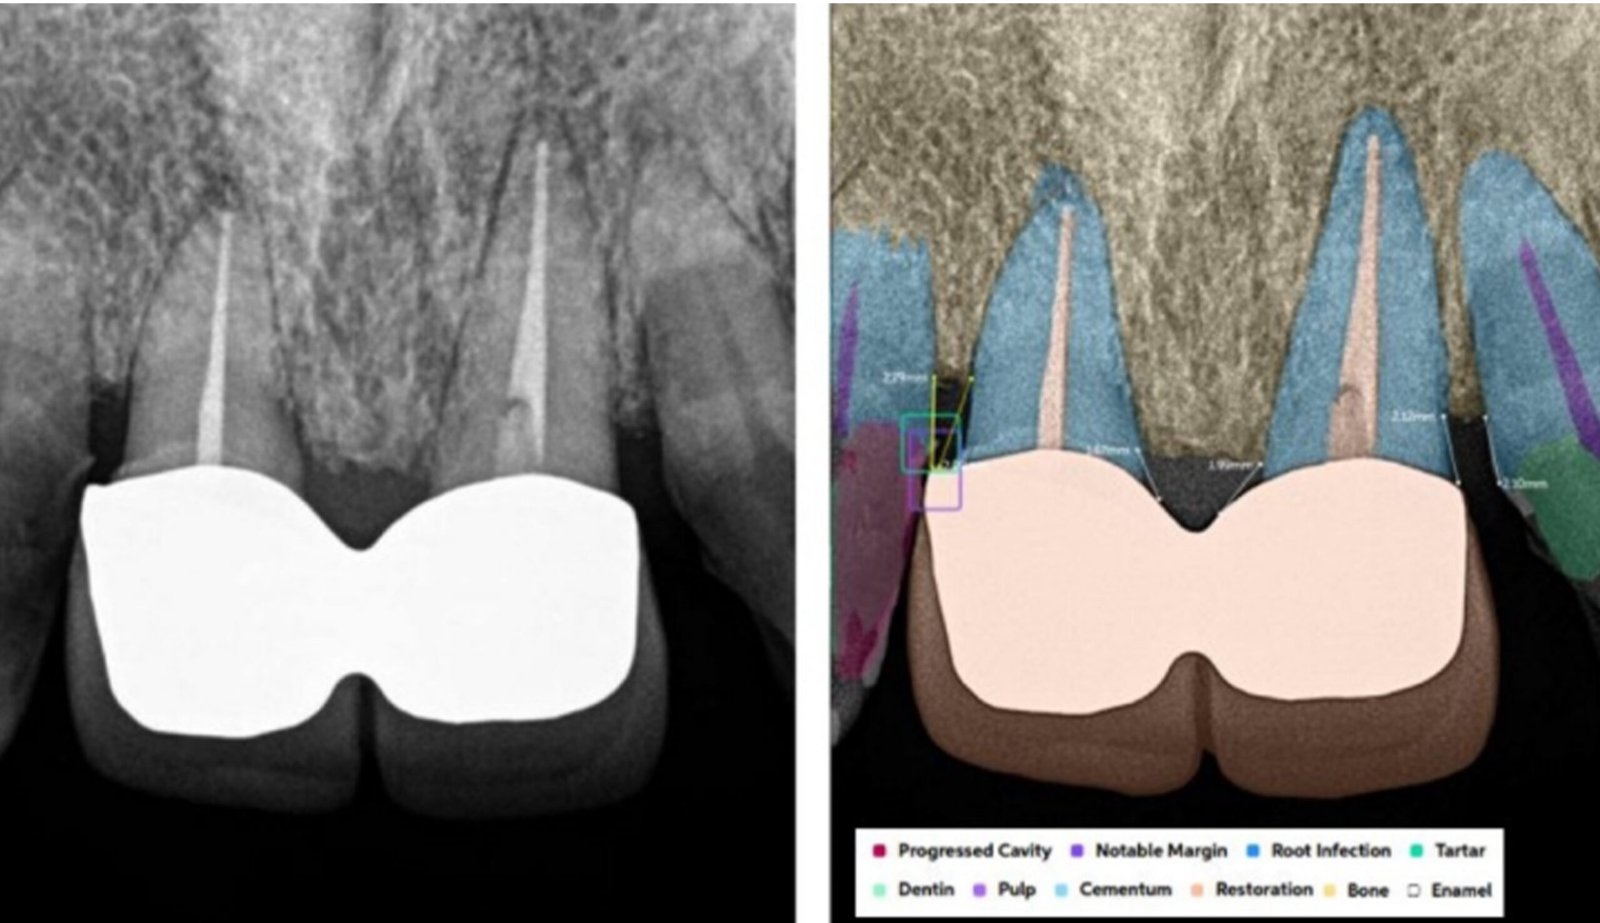

Leveraging AI-driven simulations, this segment integrates predictive modeling with clinical design. We optimize prosthetic, implant, and restorative solutions by forecasting mechanical performance, identifying risk areas, and supporting data-driven treatment planning.